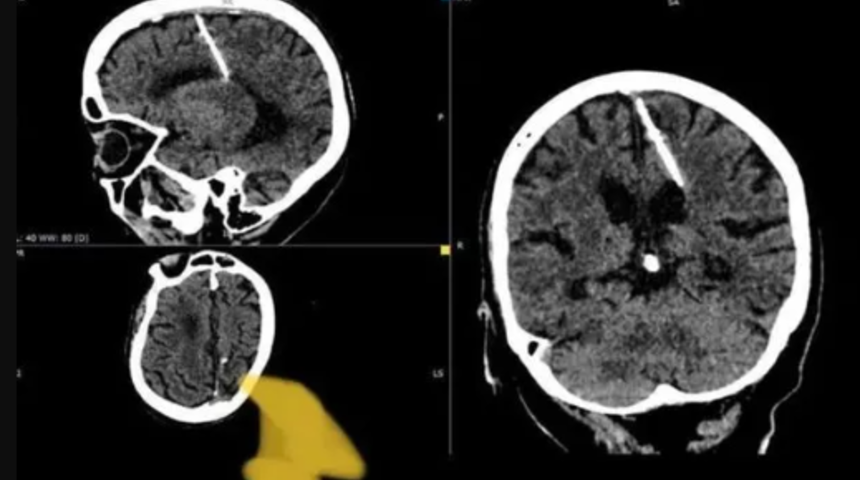

80 yaşındaki ismi açıklanmayan bir kadın doğumundan itibaren beyninde bulunan bir iğneyle yaşadı. Doktorların CAT taraması sırasında fark ettikleri iğne herhangi bir sağlık sorununa neden olmadığı ve ameliyat yapılması durumunda daha da kötüleşme ihtimali olduğu için çıkartılmaması tercih etti. İğnenin beyinde bulunma nedeni ise şaşkınlık yarattı.

80 yaşındaki kadın, bebekliğinde yaşadığı korkunç olayın ardından beyninde bulunan 3 cm uzunluğundaki iğneyle yaşadı. Doktorlar, yaşlı kadının, II. Dünya Savaşı'nda ailelerin hayatta kalma mücadelesi verdiği ve bazılarının bebek öldürmeye başvurduğu sırada ebeveynleri tarafından başarısız bir öldürme girişiminin kurbanı olduğunu keşfetti. Yıllarca beyninde bulunan iğneyle yaşayan yaşlı kadın yapılan incelemede iğnenin herhangi bir sağlık sorununa neden olmadığı belirtildiği için cerrahi işlem uygulanmadı.

Japonya'nın kuzeyindeki bir ada olan Sakhalin'de doğan ve Rusya'da yaşamaya başlayan 80 yaşındaki kadın, iğnenin başının üst kısmında fontanel adı verilen yumuşak bir noktadan girmesi nedeniyle hayatta kalmayı başardı.